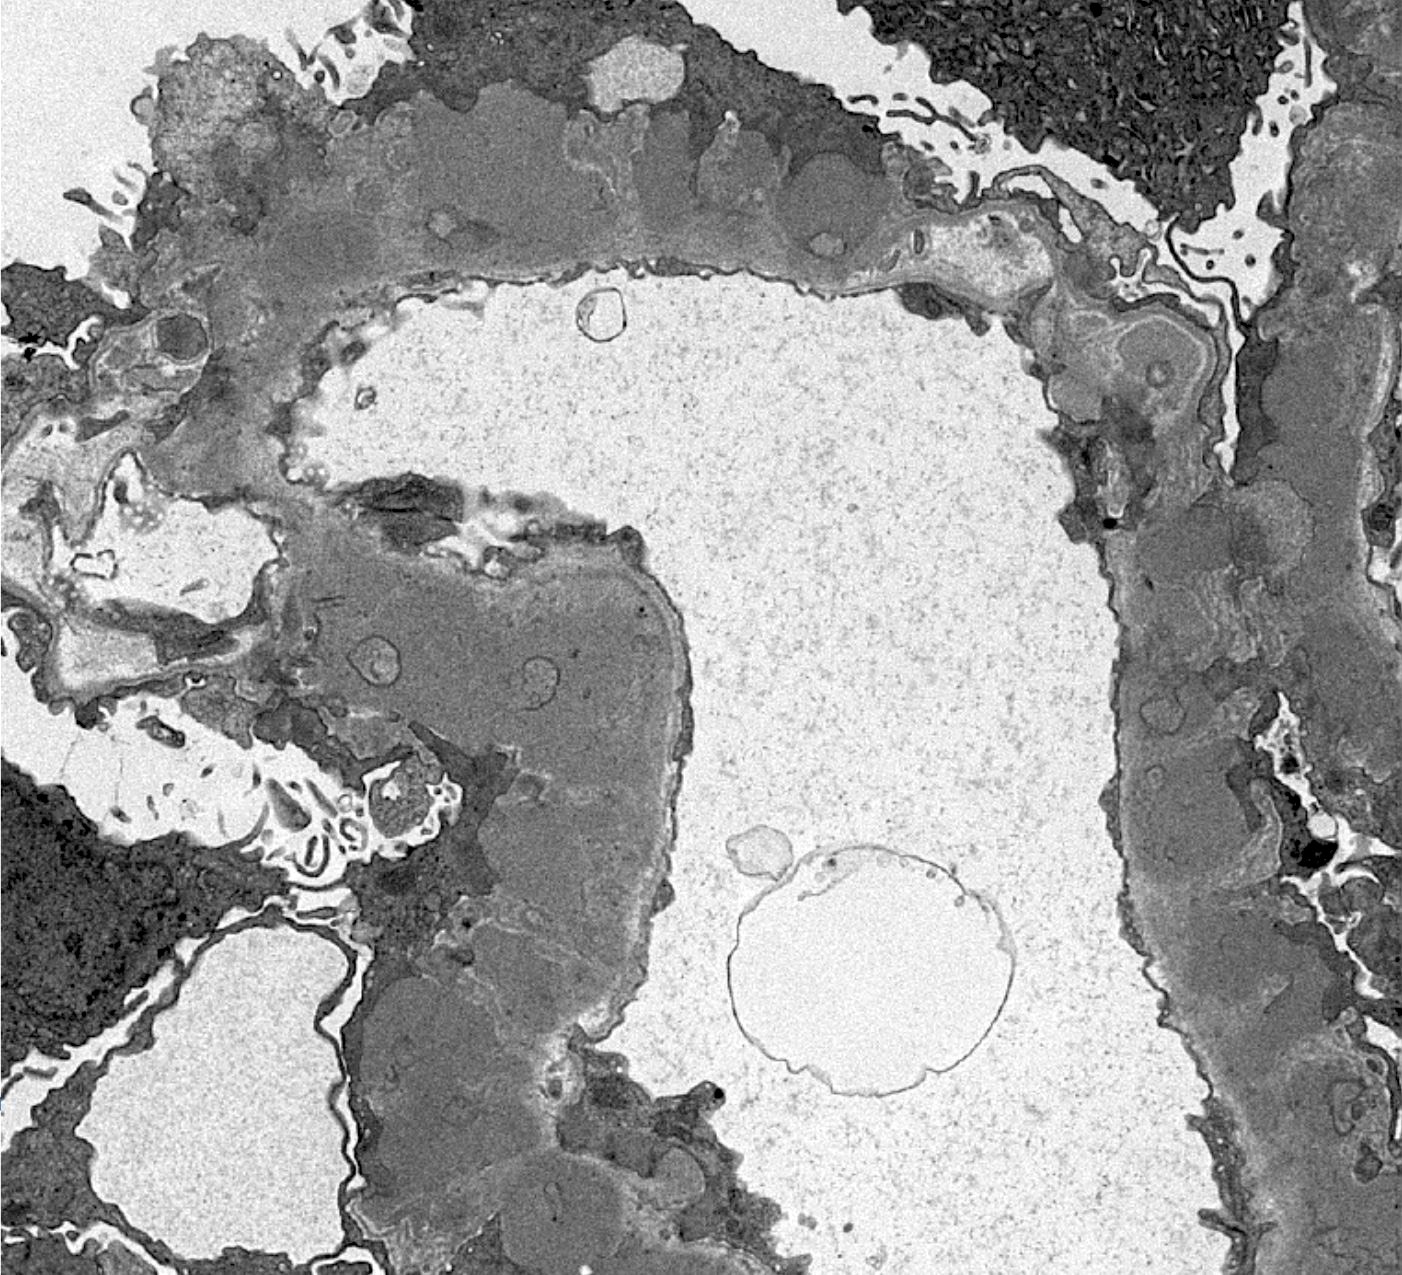

Electron microscopy description

- Electron microscopy confirms the subepithelial localization of electron dense deposits

- 4 stages:

- Scattered electron dense deposits on the epithelial side of the glomerular basement membrane

- Subepithelial deposits with basement membrane material (spikes) between deposits

- Subepithelial (or intramembranous) deposits with basement membrane material between and surrounding deposits

- Electron lucent areas represent probable resorption of prior subepithelial immune complexes

- References: Colvin: Diagnostic Pathology - Kidney Diseases, 2nd Edition, 2015, Zhou: Silva's Diagnostic Renal Pathology, 2nd Edition, 2017

Electron microscopy images

Contributed by Ana Belén Larqué, M.D., Ph.D. and Jonathan E. Zuckerman, M.D., Ph.D.